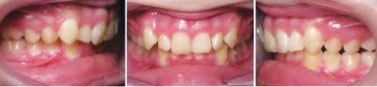

Figs. 10a-b:Final results after an additional 10 months in aligners, changed weekly. (Upper and lower: 25 each.)

Fig. 10a

Fig. 10b

Figs. 12a-d: At follow-up observations one year after treatment, the patient demonstrates stability in overjet, molar and canine class, and soft-tissue profile convexity. Interdigitation of posterior teeth is excellent. Tooth #25 has moved slightly lingually because of inconsistent retainer wear.

Fig. 12a

Fig. 12b

Fig. 12c

Fig. 12d